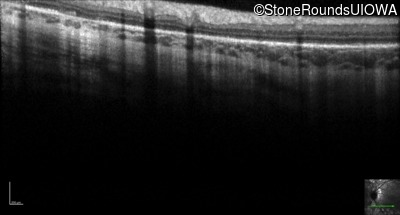

Infrared Fundus Photograph - Right - 20/32

Exemplar